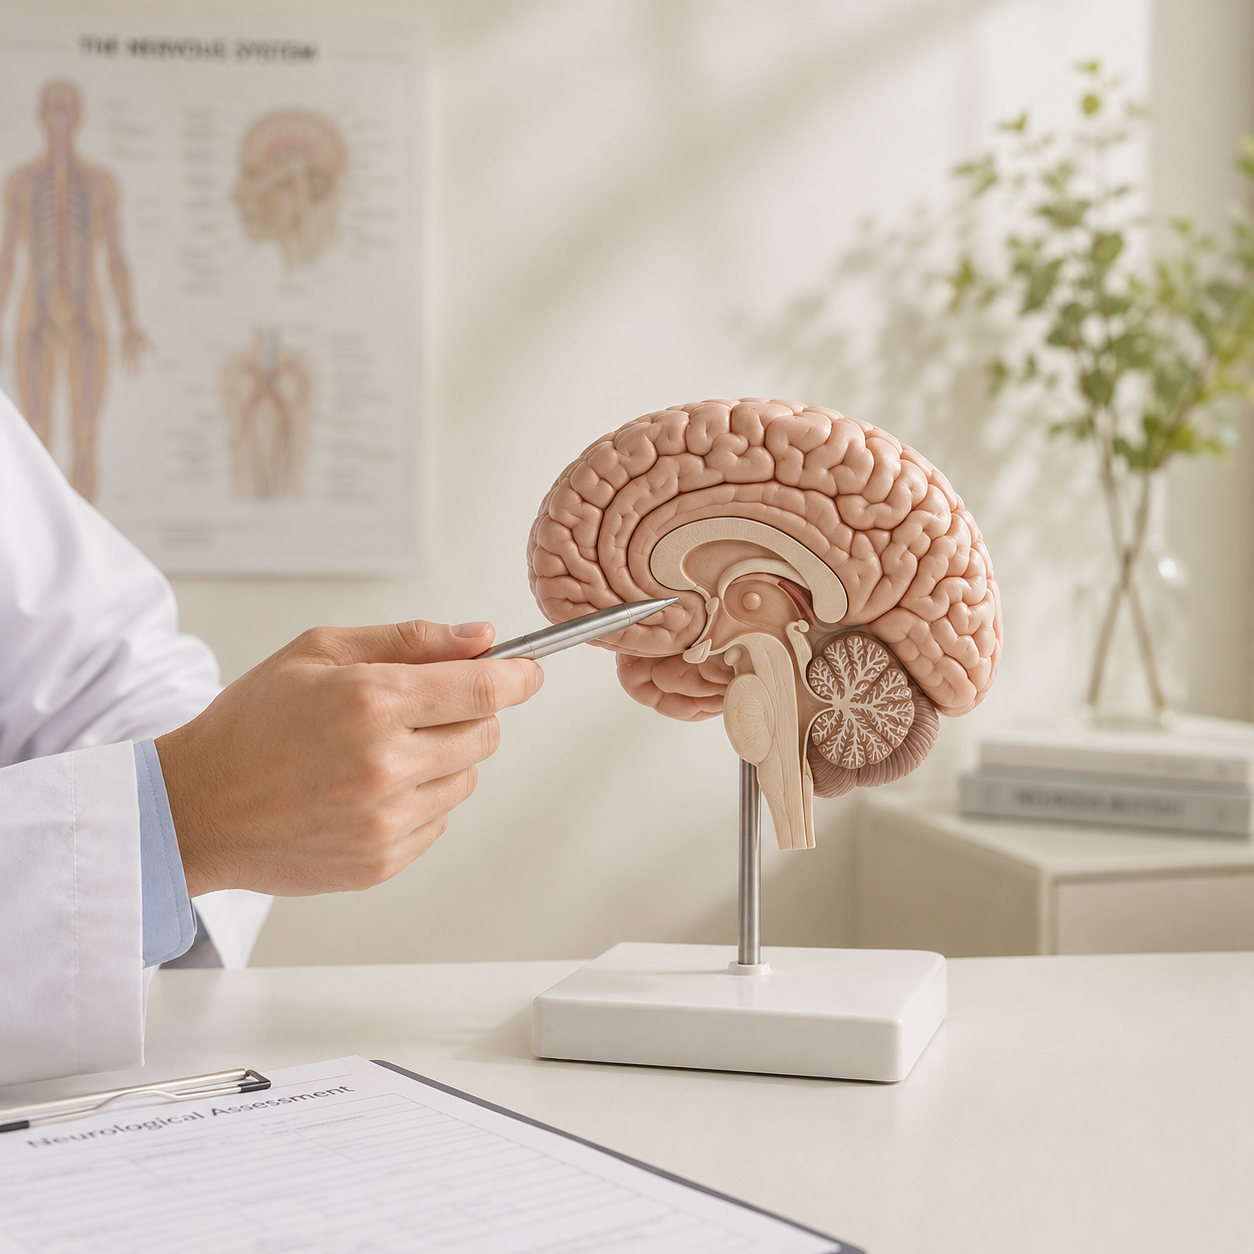

ACTIVATE YOUR BODY’S SELF-HEALING POWER

Neurological Rehab & Acupuncture in North York & Stouffville

Complete Balance: Your Multidisciplinary Rehab Clinic for Neurological, Spinal, Internal & Psychological Conditions. Holistic Care Designed to Help You Reach Your Full Potential—Drug-Free, Non-Surgical Solutions for Inflammatory Disorders

Welcome to Complete Balance Rehab Toronto

Complete Balance Neuro Acupuncture Clinic is a traditional and integrative health clinic in Toronto, dedicated to bridging gaps in the healthcare system through patient-centred, multidisciplinary care.

Integrated Zhu’s Scalp Acupuncture Clinic

The only clinic in Canada combining Zhu’s Scalp Acupuncture with coordinated neurological physiotherapy and chiropractic care.

Urgent Neurological Support

Time-sensitive integrative care for stroke, traumatic brain injury, and complex neurological conditions.